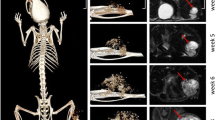

Micro-CT analysis

The bone lesions were comparable between the murine models and the human disease. A high prevalence of mandibular osteolytic lesions was observed in the HOS1544 and the AT2015-induced PDX models. More osteogenic features were noted in the MOS-J model and in the PDX induced with a human tumor fragment (Fig. 4a, b). The quantitative analysis of bone parameters in the HOS1544 model in comparison with contralateral normal mandible in mice showed a trend of tumor induced bone lysis, as revealed by the decrease of BV, BV/TV, Tb.Th, Tb.N and the increase of Tb.Sp but with non-statistical significance (Table 1).

Large osteogenic lesions with a high level of periosteal reaction were observed in the PDX models induced in long bones, particularly those induced with AT2015 tumor cells (Fig. 4c).